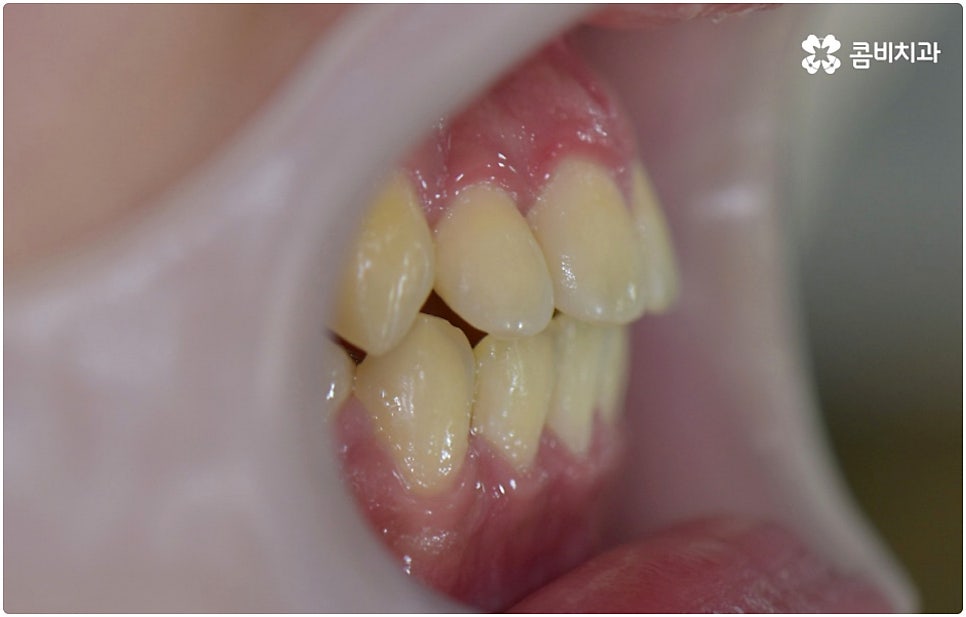

부정교합은 부정교합 1급, 부정교합 2급, 부정교합 3급 이렇게 세가지 종류로 나눌 수 있는데요. 부정교합 1급은 이를 다물었을 때 위아래 어금니는 잘 맞물리지만 덧니가 있거나 치아 사이가 살짝 벌어져 있는 경우처럼 치열이 삐뚤어진 경우를 말하는 것으로 골격이나 구조적인 부분에는 크게 문제가 없기 때문에 정도가 심하지 않다면 보다 빠르고 간편한 교정 치료가 가능한 케이스라고 할 수 있어요. 부정교합 2급은 상악이 하악보다 더 튀어나온 상태로 위에서 언급했던 무턱, 돌출입이 여기에 속하며 반대로 부정교합 3급 은 주걱턱처럼 하악이 상악보다 튀어나온 상태를 의미하고 있습니다.

부정교합 2급, 부정교합 3급 과 같이 구조적인 부분에 원인이 있는 문제라면 잇몸뼈가 다 굳고 난 다음인 중장년 성인분들의 경우 교정 치료를 받는 것이 과연 부정교합 개선에 효과가 있을까 궁금해 하실 수 있어요. 특히 턱관절 이상 문제는 수술을 통해서만 고칠 수 있다고 알고 계셨던 분들은 부담을 느끼고 치료를 미루셨을 수 있는데요. 물론 성인분들의 경우 상황에 따라, 예를 들어 정도가 매우 심한 부정교합 3급 케이스라면 악교정수술을 받아야 할 수도 있습니다. 또한 대부분의 부정교합 2급, 부정교합 3급 케이스들 같은 경우 초등학교 고학년에서 중학교 저학년 사이에 교정 치료를 시작하는 것이 좋다고 권유하는 것도 사실인데요, 그 이유는 아무래도 치아 이동 속도가 빠르고 전반적인 발달 상황에 맞추어 자연스럽게 치료를 진행할 수 있는 성장기의 특성상 이 시기부터 지속적으로 턱뼈 크기 부조화를 조절하고 상하악의 올바른 성장을 유도하는 게 보다 효율적이기 때문이라고 할 수 있어요.